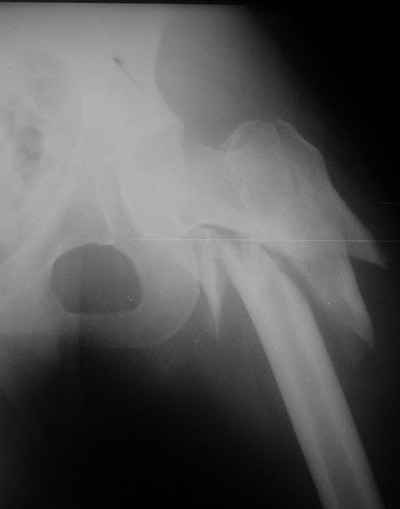

Девушка 21 года 02.10.07 г. пострадала в результате падения с высоты 4-го этажа при пожаре в одном из студенческих общежитий г. Москвы. Получила тяжелую сочетанную травму, в том числе закрытый оскольчатый чрез- и подвертельный перелом левой бедренной кости. Лечилась в одной из больниц столицы. Бедро было фиксировано при помощи скелетного вытяжения. Через полтора месяца после травмы переведена в институт им. Склифосовского. У больной имелись: поддиафрагмальный абсцесс, трахеопищеводный свищ, трахеостома, гастростома, несостоятельность швов раны передней брюшной стенки, укорочение левого бедра на 10 см (рентгенограммы при поступлении - рис 1.). В середине декабря был наложен спицестержневой аппарат, с помощью которого к сегодняшнему удалось устранить укорочение бедра (рис. 2). В течение последних 4-х дней устраняем смещение дистального отломка бедренной кости по ширине. Раны на передней брюшной стенке почти зажили. Температура тела и лабораторные показатели нормальные. Планируем выполнить закрытый остеосинтез левой бедренной кости удлиненным проксимальным бедренным штифтом производства фирмы "Остеомед". Нас смущает, что малый вертел бедренной кости остается значительно смещенным проксимально и кнутри.

Мы закончили репозицию отломков бедренной кости в аппарате (рис. 1, 2) у нашей пациентки и на прошлой неделе сделали ей вторую операцию. Штифт удалось ввести закрыто. Верхний шеечный винт держался очень плохо, поэтому мы его убрали и решили не ставить. Нижний держал очень плотно. Рентгенограммы после операции прилагаю (рис. 3,4). Пока не получилось сделать нормальный аксиальный снимок (больная с трудом сгибает и отводит ногу в тазобедренном суставе). Пока сделали боковую проекцию в положении на здоровом боку со сгибанием здоровой ноги.